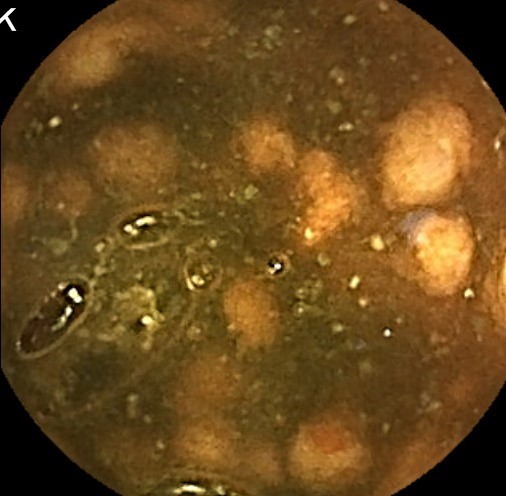

Capsule Endoscopy: Ileum Terminale, Lymphoid Hyperplasia

Capsule Endoscopy: Ileum Terminale, Lymphoid Hyperplasia. Just click on a picture!